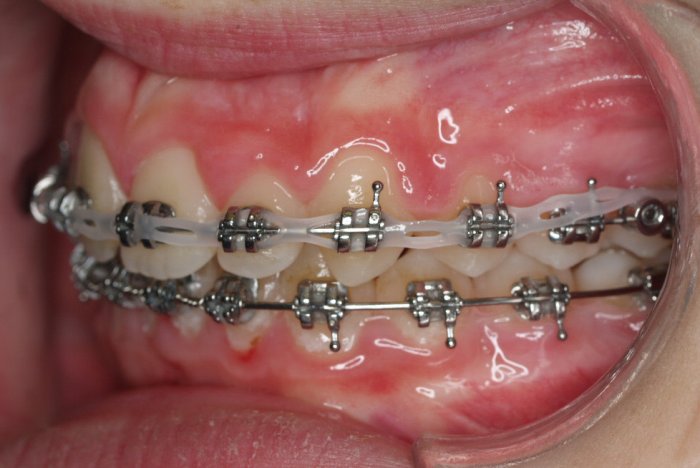

Un “diastema” es una separación extraordinariamente grande entre dos o más dientes. La mayoría de las veces, el diastema aparece entre los dos dientes delanteros superiores. Muchos niños tienen diastema cuando se les caen los dientes de leche, pero en la mayoría de los casos esta distancia desaparece cuando salen los dientes permanentes.

Los diastemas pueden deberse a una diferencia en los tamaños de los dientes, a la falta de algún diente o a que el frenillo labial sea demasiado grande. El frenillo labial es el tejido que va desde el interior del labio hasta la encía, en el lugar donde se sitúan los dos dientes delanteros superiores. Los diastemas también pueden deberse a problemas en la alineación de la boca, como la sobremordida horizontal o la protrusión de los dientes1.

- Realizar un tratamiento ortodóncico para mover los dientes y cerrar el diastema.

Si su frenillo labial es demasiado grande, puede que le remitan a un especialista para someterse a un procedimiento quirúrgico llamado frenectomía. Este procedimiento consiste en cortar el frenillo y volverlo a colocar para permitir que tenga más flexibilidad. Cuando la frenectomía se realiza en un niño, el espacio puede llegar a cerrarse por sí solo. Si se trata de un adolescente o un adulto, puede que sea necesario cerrarlo con ortodoncia. Es esencial acudir al dentista para saber cuál de estas opciones es la adecuada en su caso.